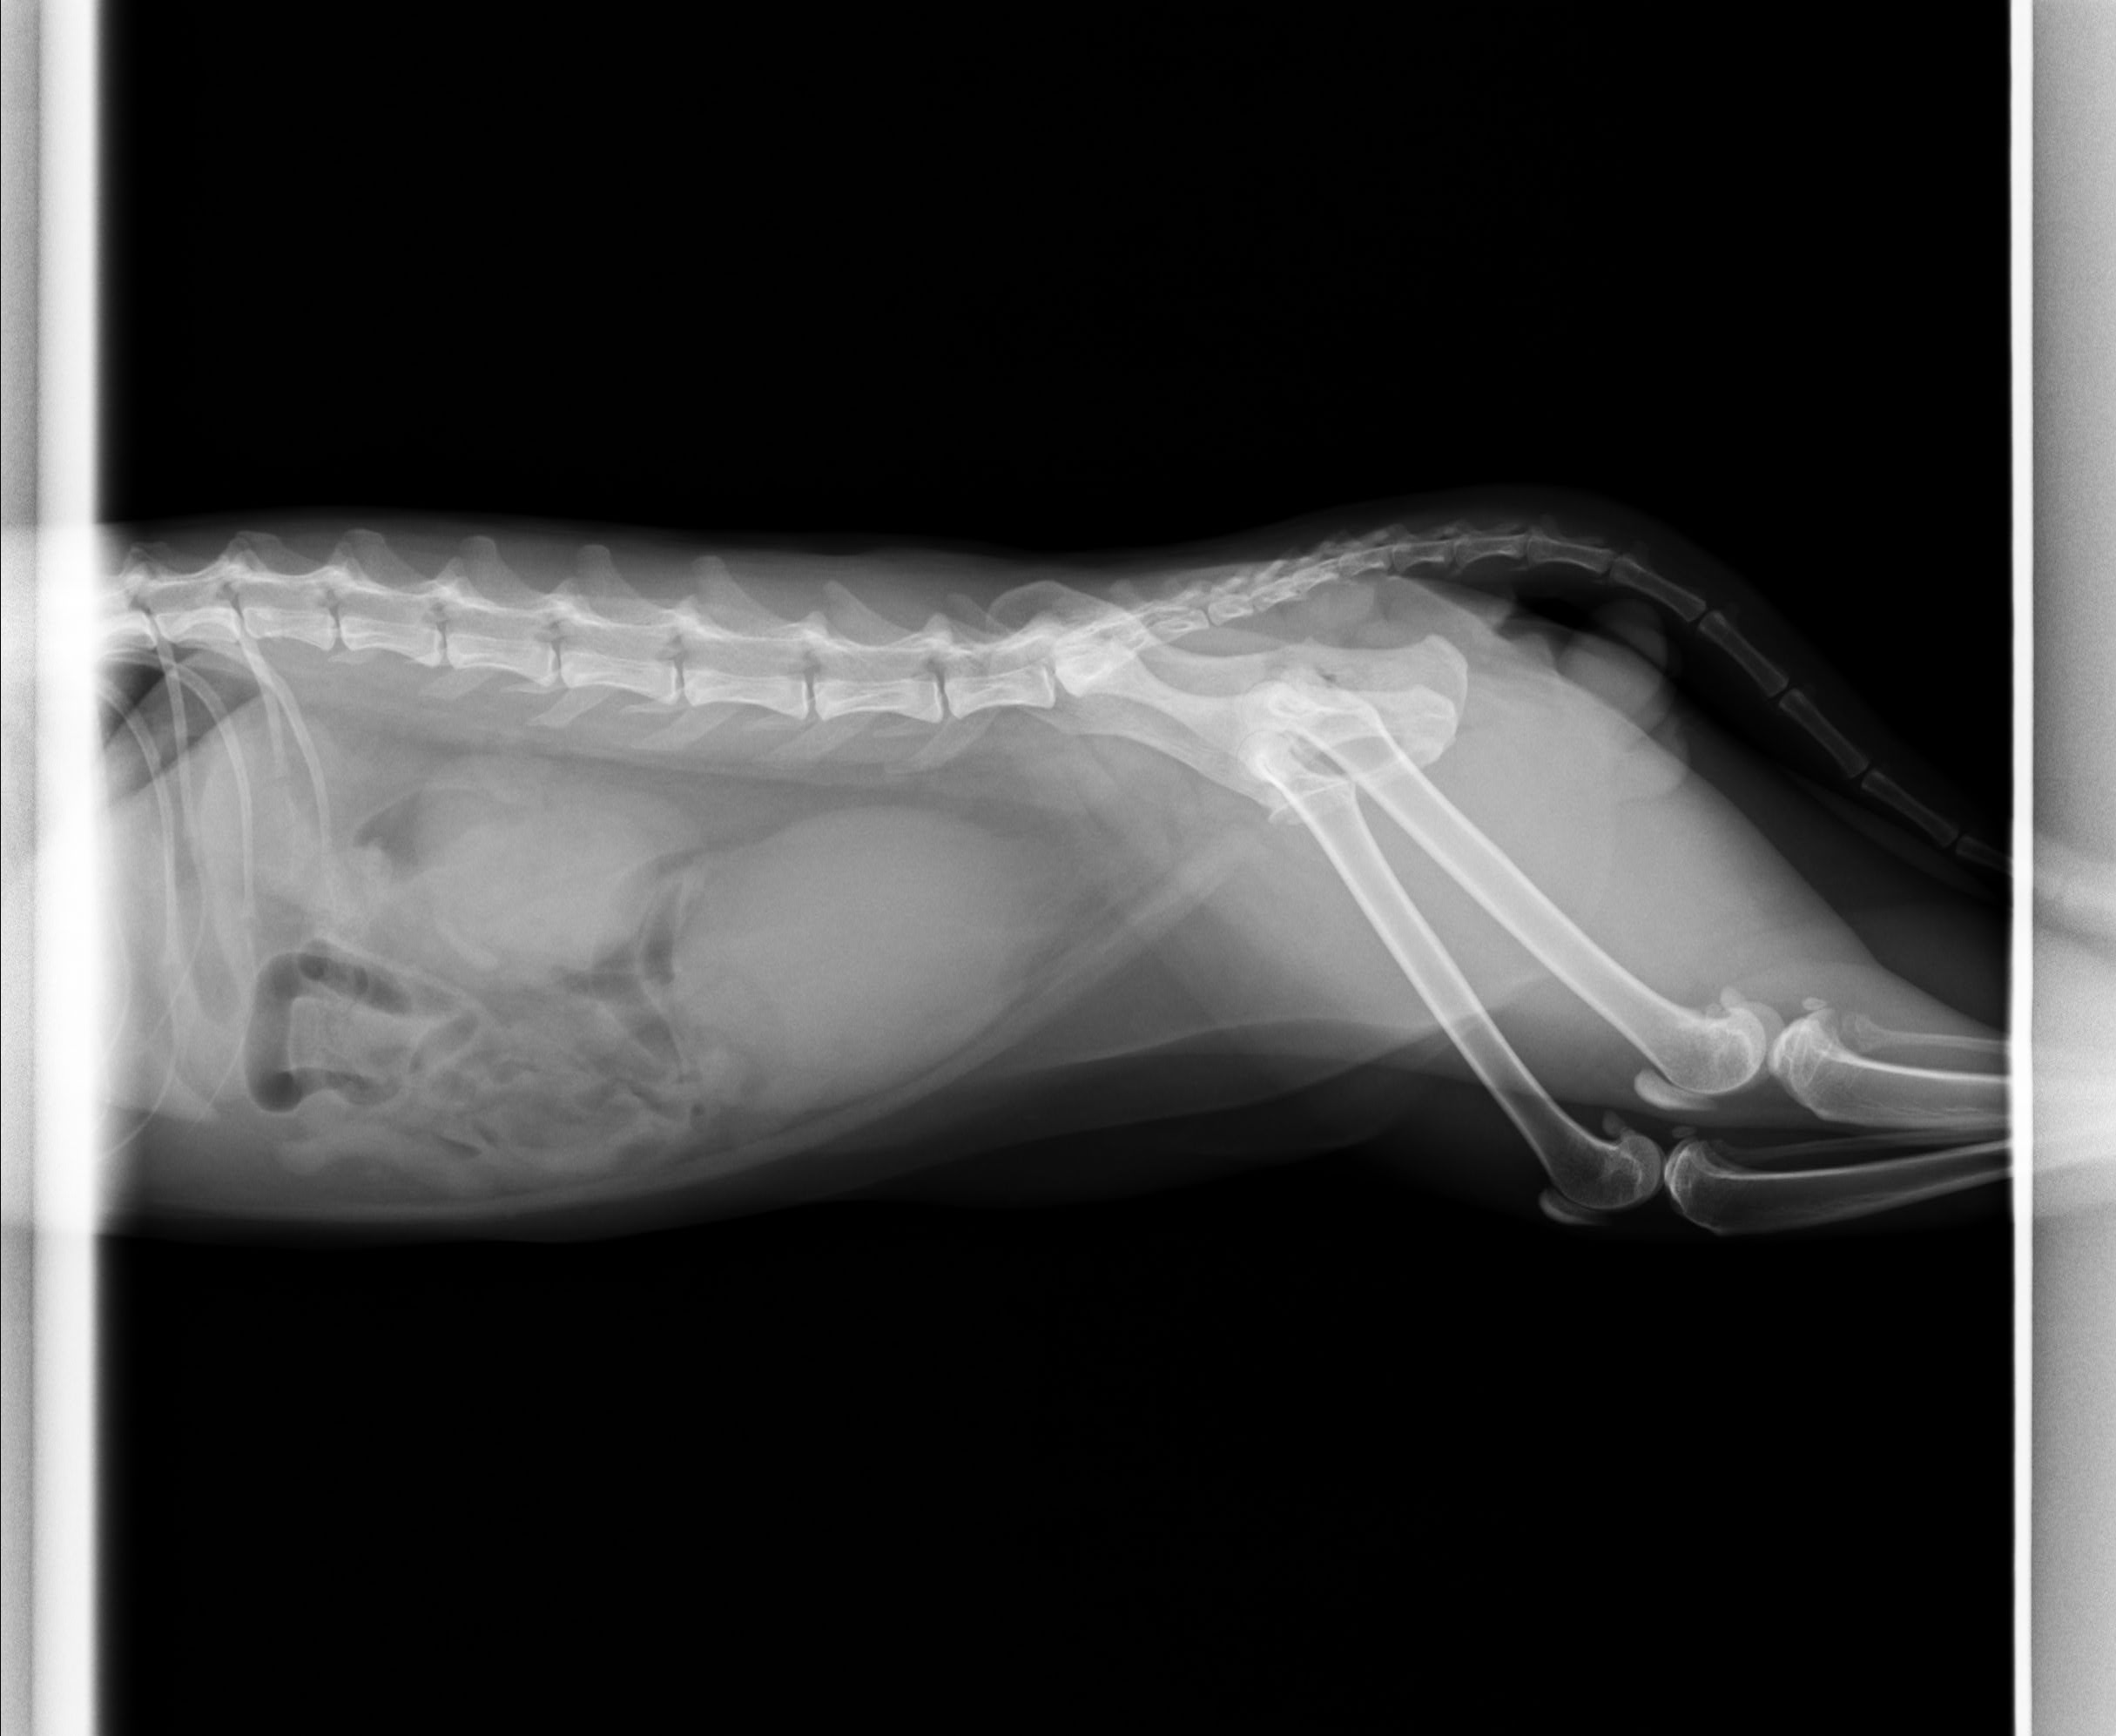

初期症状としては頻繁な排尿姿勢、トイレ内での鳴き声、陰部を過剰に舐める、嘔吐、食欲不振、沈うつなどが見られます。身体検査では膀胱が硬く膨張し、腹部に痛みを示すことがあります。診断は視診、触診、尿道カテーテルの挿入試験による閉塞の確認に加え、血液検査による高カリウム血症や腎機能異常の確認、レントゲンや超音波検査による尿石や膀胱壁の評価を行います。